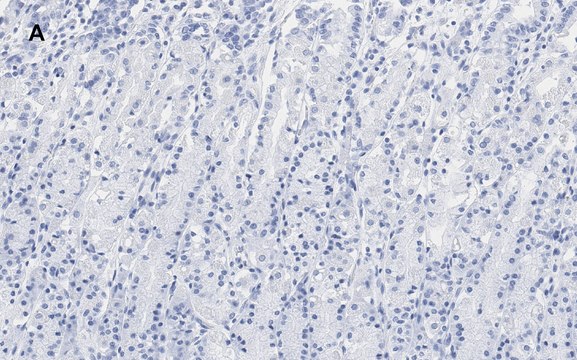

Immunohistochemistry (Paraffin) Analysis: A 1:100 dilution from a representative lot detected IKB alpha in human stomach tissue sections.